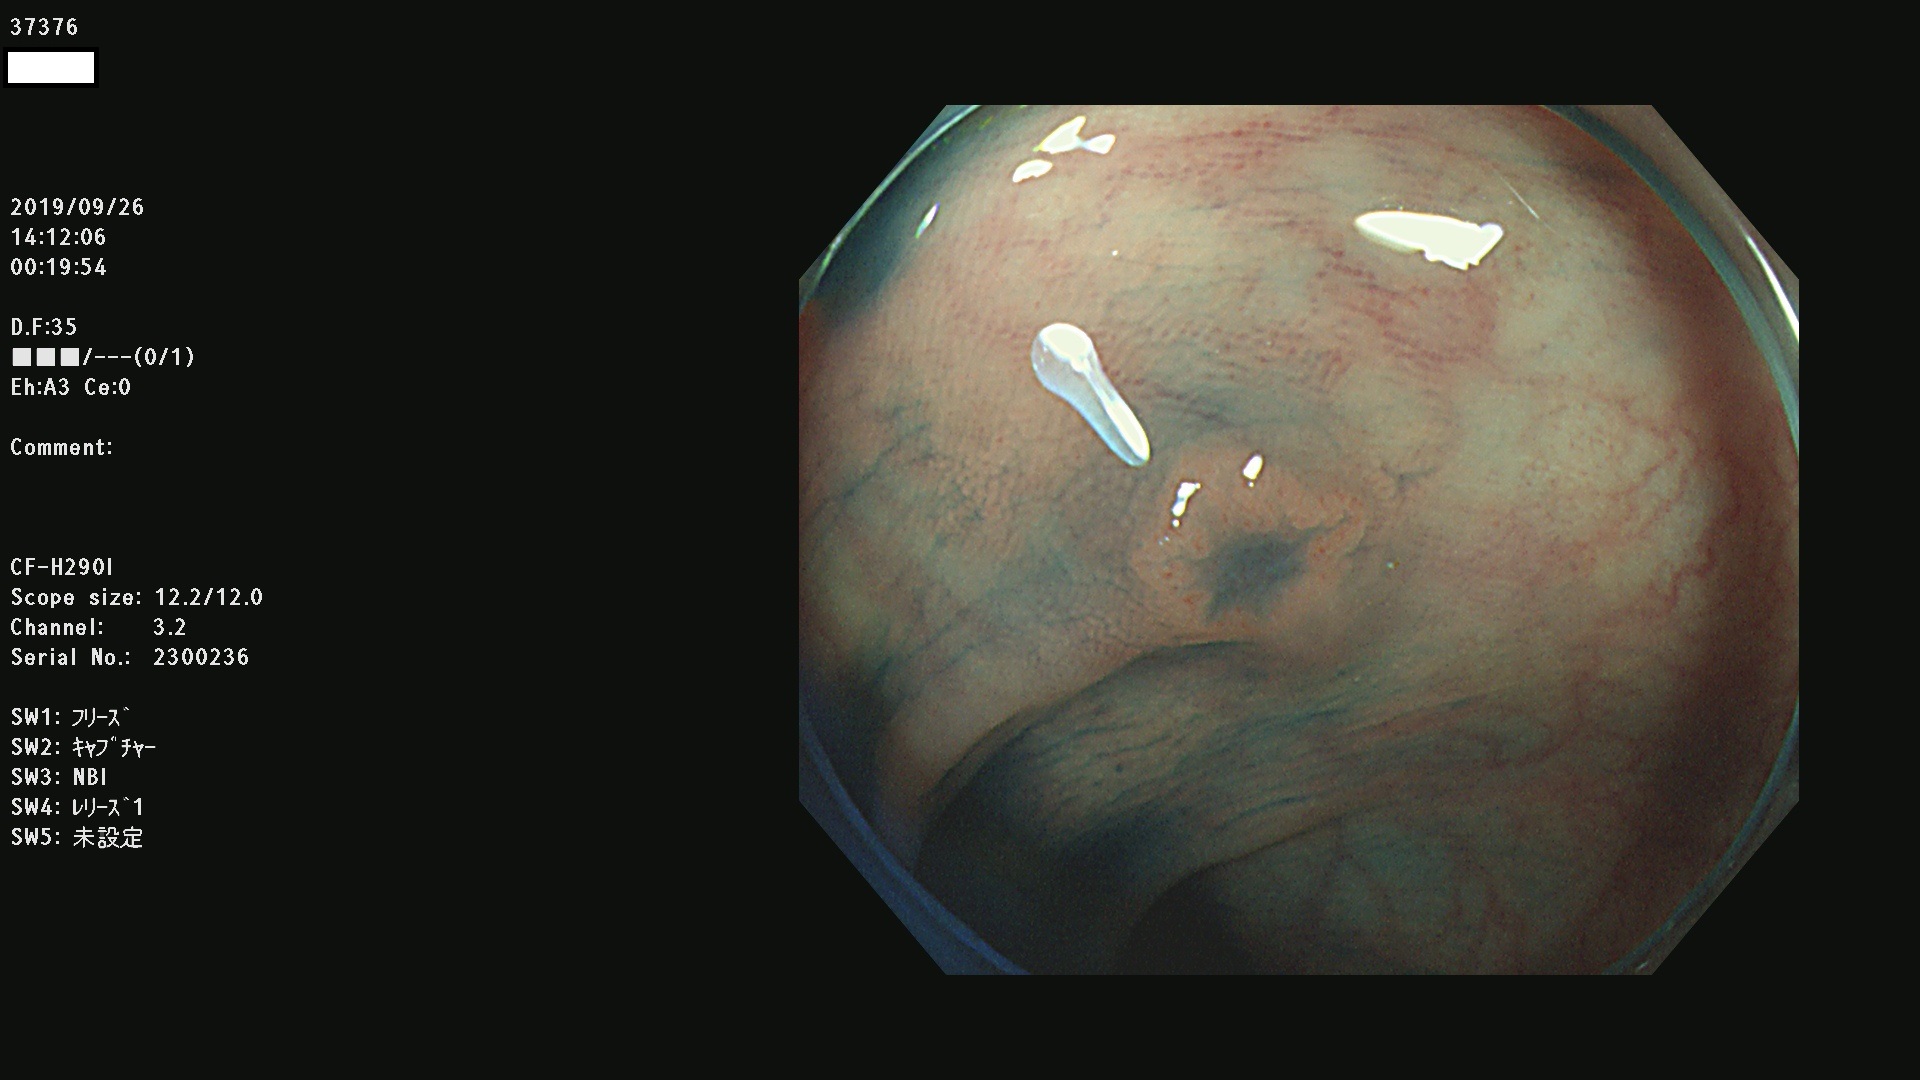

37300(SSAPのみ) 37301 37303 37304 37306 37307 37308 37309 37312 37313 37315(SSAPのみ) 37316 37317(SSAPのみ) 37319 37321(SSAPのみ) 37322 37323 37324 37325 37326 37328(SSAPのみ) 37329 37330 37331 37332(SSAPのみ) 37333 37334 37336 37337 37338 37340 37342 37343(SSAPのみ) 37344 37345 37346 37347 37348 37352(SSAPのみ) 37353 37354 37355 37356 37358 37360 37361(SSAPのみ) 37362 37363 37366 37367 37369 37370 37371 37372(SSAPのみ) 37375 37376 37377 37380 37381(SSAPのみ) 37382 37383 37384 37385(SSAPのみ) 37386 37387 37388 37389 37390 37392(SSAPのみ) 37393 37394 37395 37396(SSAPのみ) 37397 37398(SSAPのみ) 37399

発見困難で危険性の高い平坦型病変(上記100名より抽出) )